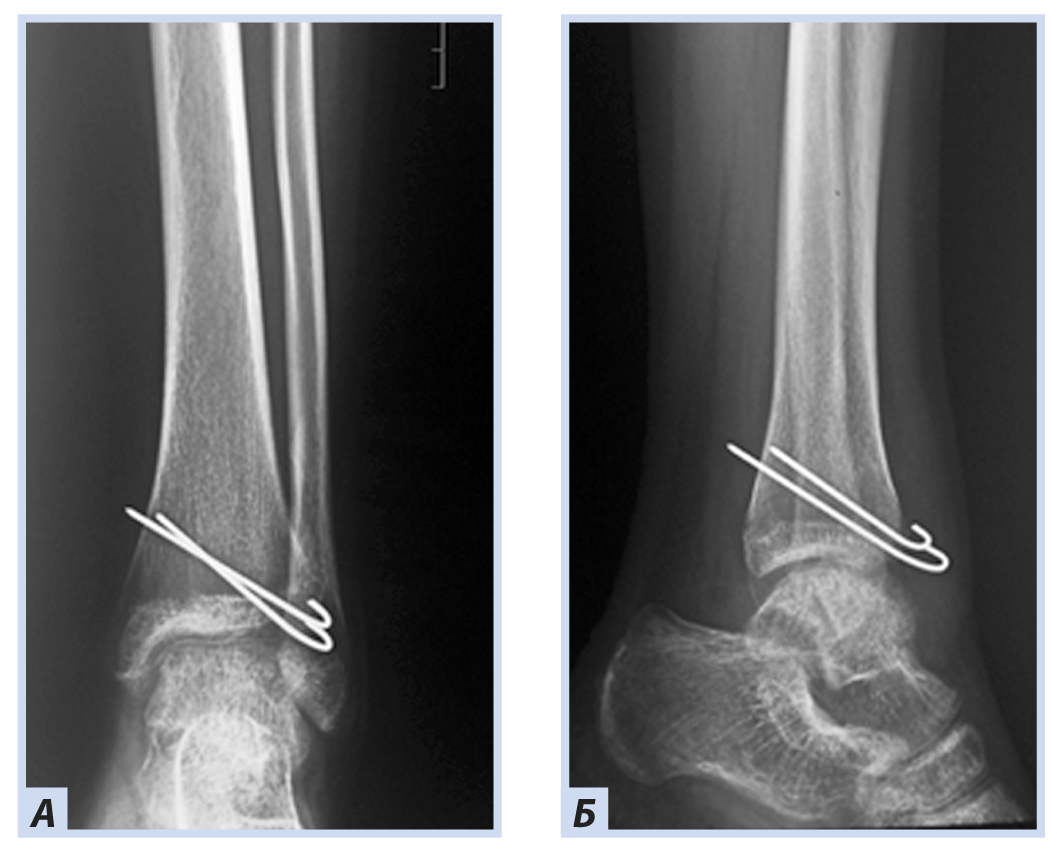

Клиническое наблюдение 1

Девочка, 10 лет, диагноз: «Закрытый дистальный остеоэпифизеолиз правой большеберцовой кости, Salter–Harris, II тип». Травму получила, упав с самоката, вследствие чрезмерного сгибания стопы кзади. По механизму травмы — ротационно-флексионный перелом дистального отдела костей голени. По данным компьютерной томографии выявлена значительная степень (5 мм) смещения отломков. Учитывая возраст больной, остеосинтез выполнен закрыто перекрещивающимися спицами. Дополнительная иммобилизация осуществлялась в задней гипсовой лонгете до коленного сустава. Контрольные рентгенограммы выполняли через 4 и 6 нед. после репозиции. Спицы удалены через 6 нед., конфигурация сустава восстановлена полностью (рис. 1–5).

Рис. 3. Тот же пациент. Рентгенограммы дистального отдела костей правой голени. Полифокальный остеосинтез спицами: А — прямая проекция; Б — боковая проекция.